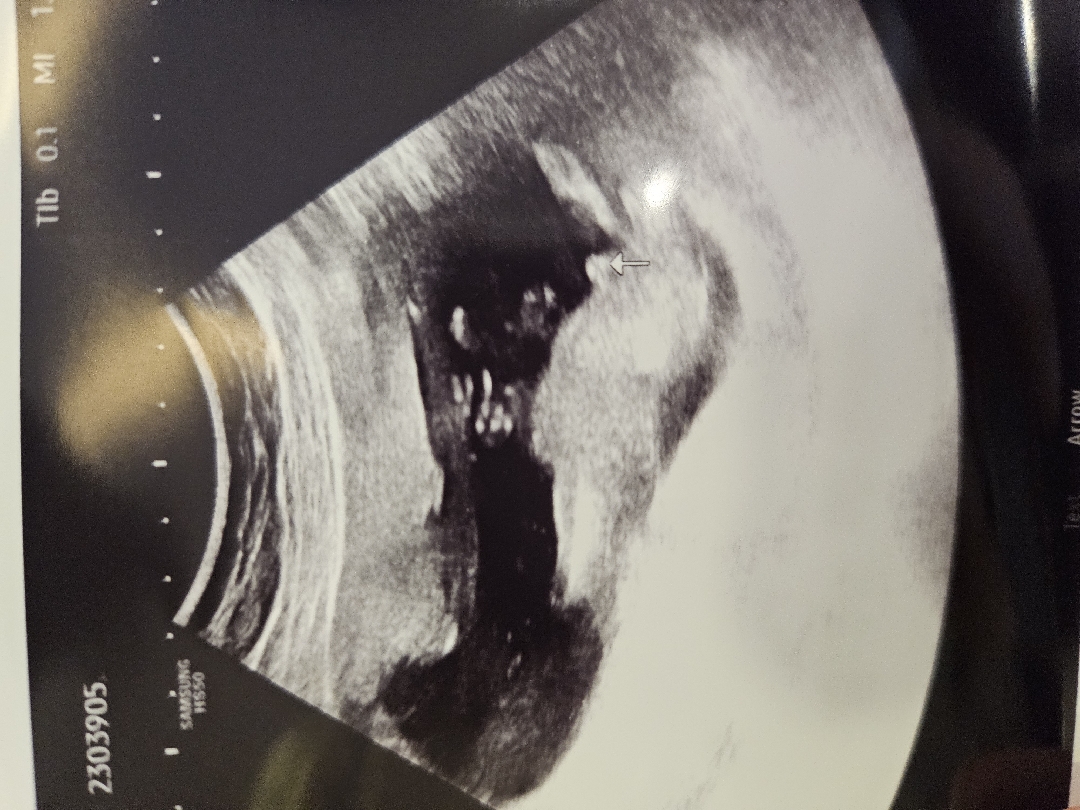

이것이 남자아이🌶 인가요!!

정말 신기하네요!! 의사쌤이 정확하게 말은 안해주시고 아직 작은거같다 라고 하셧거든용ㅎㅎ 어때 보이나요?ㅎㅎ